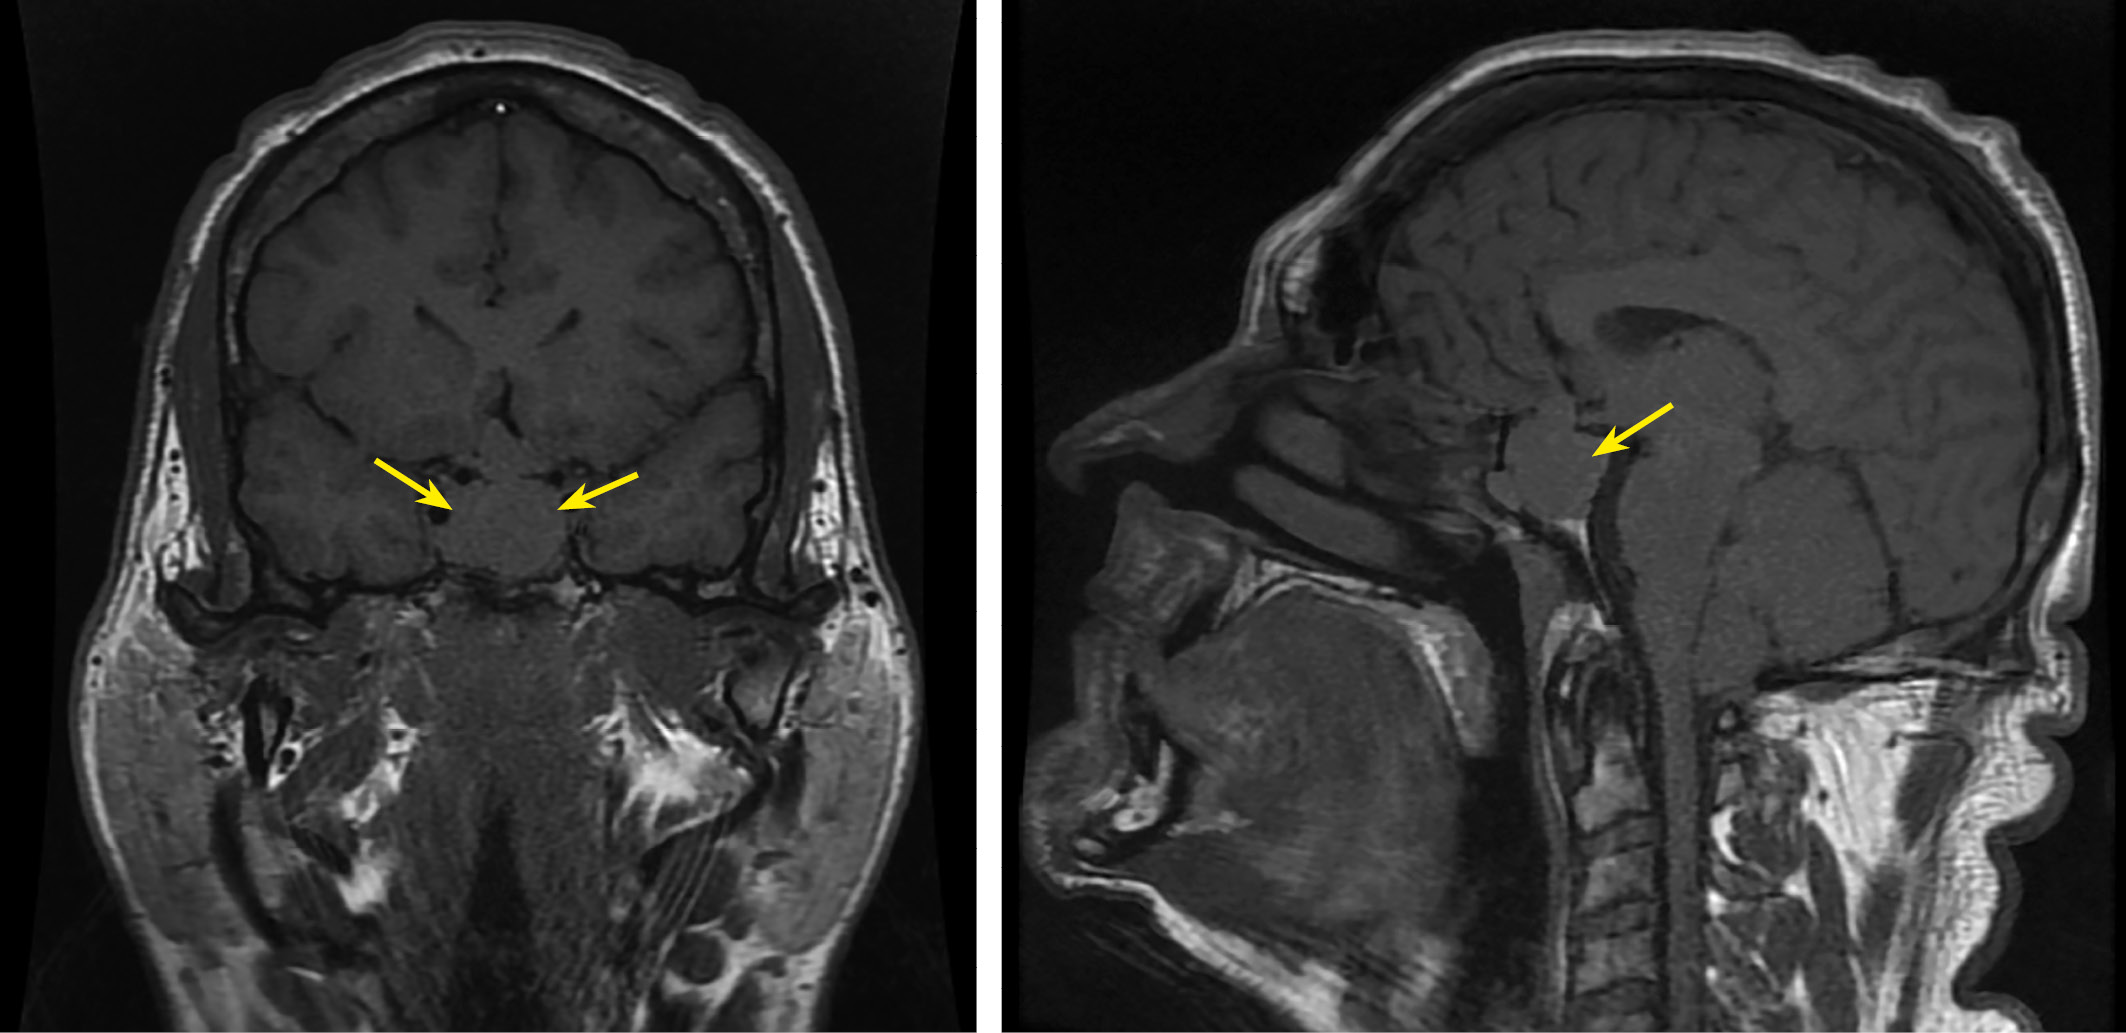

По результатам лабораторных исследований подтверждено отсутствие ремиссии акромегалии на фоне медикаментозного лечения: ИФР-1 — 527,0 нг/мл (82,0–283,0), по данным МРТ головного мозга с контрастным усилением — объемное кистозно-солидное образование с пара-, анте-, инфраселлярным распространением размерами до 18×14×20 мм (положительная динамика) (рис. 4).

Рисунок 4. МРТ головного мозга с внутривенным контрастированием пациента Д: в полости турецкого седла с пара- (D, Knosp 2), анте-, инфраселлярным распространением определяется объемное кистозно-солидное образование неправильной формы (кистозный компонент преобладает) размерами до (вертикальный — поперечный — переднезадний) 18×14×20 мм, при контрастном усилении солидный компонент замедленно накапливает контрастный препарат (относительно ткани аденогипофиза).

Figure 4. Brain MRI scan with intravenous contrast of the patient D: cystic-solid tumor of irregular shape (with predominance of cystic compenent) in the sella with para-(D, Knosp 2), ante- infrasellar growth, 18x14x20 mm in size (vertical – transverse – anteroposterior), the solid component accumulates the contrast slower than the anterior pituitary.